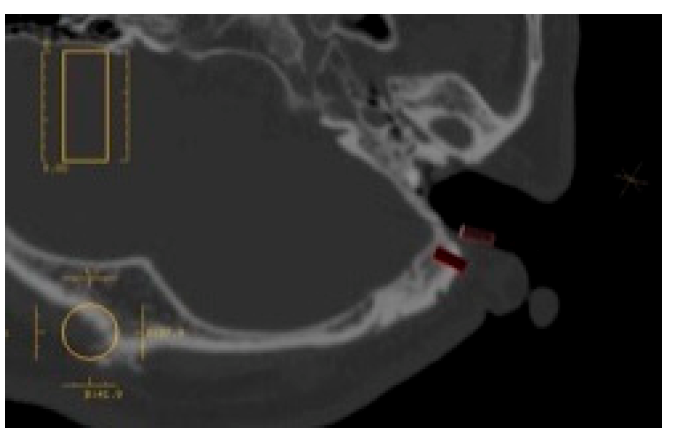

First, the CT data are obtained for use in the imaging anatomical diagnosis and simulation of the drilling positions (Figure 13). With regards to the preoperative simulation, after deciding on the location of the implant site based on the anatomical guidelines in Tjellström et al., one can use the CT images to determine if there is enough thickness to the bone to insert an implant. When planning for a navigation operation, in addition to the above, you will use the computer to create a mirror image of the unaffected ear and place this image on the affected side to get a sense of what the post-operative image may look like. For example, in the case shown in Figure 12, as a decision was already made to use the remaining elongated and deformed ear to surgically create a tragus; the mirroring of the unaffected ear helped select the section of the deformed ear that should be used as the tragus and the section that should be resected (Figure 14). Second, the surgical template with markers is fabricated; a resinous apparatus embedding two implant position markers at the drilling sites and twenty 0.5 mm metallic registration markers on the bar between the ear template and the mouthpiece fitting on the maxillary arch (Figure 15). The CT is taken again with the apparatus attached with three reflective spheres, and the registration is provided on the display (Figure 16). After the confirmation of accurate registration, the ear part of the apparatus is cut before surgery in order to let the implant positions be visible (Figure 17).

Figure 13. Preoperative implant placement simulation.

Figure 14. Using CT software, a mirror image of the healthy ear is placed on the affected ear, and the auricle resection site should be examined preoperatively.